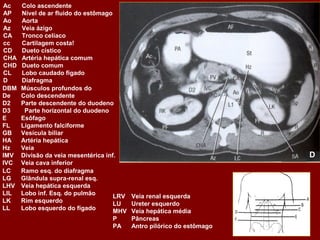

Ac Colo ascendente AP Nível de ar fluido do estômago Ao Aorta Az Veia ázigo CA Tronco celíaco cc Cartilagem costa! CD Dueto cístico CHA Artéria hepática comum CHD Dueto comum CL Lobo caudado fígado D Diafragma DBM Músculos profundos do De Colo descendente D2 Parte descendente do duodeno D3 Parte horizontal do duodeno E Esôfago FL Ligamento falciforme GB Vesícula biliar HA Artéria hepática Hz Veia IMV Divisão da veia mesentérica inf. A IVC Veia cava inferior LC Ramo esq. do diafragma LG Glândula supra-renal esq. LHV Veia hepática esquerda LIL Lobo inf. Esq. do pulmão LRV Veia renal esquerda LK Rim esquerdo LU Ureter esquerdo LL Lobo esquerdo do fígado MHV Veia hepática média P Pâncreas PA Antro pilórico do estômago

Ac Colo ascendente AP Nível de ar fluido do estômago Ao Aorta Az Veia ázigo CA Tronco celíaco cc Cartilagem costa! CD Dueto cístico CHA Artéria hepática comum CHD Dueto comum CL Lobo caudado fígado D Diafragma DBM Músculos profundos do De Colo descendente D2 Parte descendente do duodeno D3 Parte horizontal do duodeno E Esôfago FL Ligamento falciforme GB Vesícula biliar HA Artéria hepática Hz Veia IMV Divisão da veia mesentérica inf. IVC Veia cava inferior B LC Ramo esq. do diafragma LG Glândula supra-renal esq. LHV Veia hepática esquerda LIL Lobo inf. Esq. do pulmão LRV Veia renal esquerda LK Rim esquerdo LU Ureter esquerdo LL Lobo esquerdo do fígado MHV Veia hepática média P Pâncreas PA Antro pilórico do estômago

Ac Colo ascendente AP Nível de ar fluido do estômago Ao Aorta Az Veia ázigo CA Tronco celíaco cc Cartilagem costa! CD Ducto cístico CHA Artéria hepática comum CHD Ducto comum CL Lobo caudado fígado D Diafragma DBM Músculos para vertebrais De Colo descendente D2 Parte descendente do duodeno D3 Parte horizontal do duodeno E Esôfago FL Ligamento falciforme GB Vesícula biliar HA Artéria hepática Hz Veia IMV Divisão da veia mesentérica inf. C IVC Veia cava inferior LC Ramo esq. do diafragma LG Glândula supra-renal esq. LHV Veia hepática esquerda LIL Lobo inf. Esq. do pulmão LRV Veia renal esquerda LK Rim esquerdo LU Ureter esquerdo LL Lobo esquerdo do fígado MHV Veia hepática média P Pâncreas PA Antro pilórico do estômago

Ac Colo ascendente AP Nível de ar fluido do estômago Ao Aorta Az Veia ázigo CA Tronco celíaco cc Cartilagem costa! CD Dueto cístico CHA Artéria hepática comum CHD Dueto comum CL Lobo caudado fígado D Diafragma DBM Músculos profundos do De Colo descendente D2 Parte descendente do duodeno D3 Parte horizontal do duodeno E Esôfago FL Ligamento falciforme GB Vesícula biliar HA Artéria hepática Hz Veia IMV Divisão da veia mesentérica inf. D IVC Veia cava inferior LC Ramo esq. do diafragma LG Glândula supra-renal esq. LHV Veia hepática esquerda LIL Lobo inf. Esq. do pulmão LRV Veia renal esquerda LK Rim esquerdo LU Ureter esquerdo LL Lobo esquerdo do fígado MHV Veia hepática média P Pâncreas PA Antro pilórico do estômago

PB Corpo do pâncreas PC Confluência portal PF Gordura perirrenal PH Cabeça do pâncreas PS Músculo psoas PT Cauda do pâncreas PU Processo uncinado do pâncreas PV(R) Ramo direito da veia porta QL Músculo quadrado do lombo R Costela RA Músculo reto do abdome RC Pilar direito do diafragma RF Gordura retroperitoneal RG Glândula supra-renal dir. RHV Veia hepática direita RIL Lobo inf. do pulmão dir. RK Rim direito RL Lobo direito do fígado RP Pelve renal RPV Veia porta RRA Artéria renal direita E RRV Veia renal direita RU Ureter direito S Processo espinhoso SA Artéria esplênica SC Medula espinal Sp Baço SF Flexura esq. do colo St Estômago SI Intestino delgado SV Veia esplênica SMA Artéria mesentérica sup. Tc Coto transverso SMV Veia mesentérica sup. TVP Processo transverso Xp Processo xifóide

PB Corpo do pâncreas PC Confluência portal PF Gordura perirrenal PH Cabeça do pâncreas PS Músculo psoas PT Cauda do pâncreas PU Processo uncinado do pâncreas PV(R) Ramo direito da veia porta QL Músculo quadrado do lombo R Costela RA Músculo reto do abdome RC Pilar direito do diafragma RF Gordura retroperitoneal RG Glândula supra-renal dir. RHV Veia hepática direita RIL Lobo inf. do pulmão dir. RK Rim direito RL Lobo direito do fígado RP Pelve renal RPV Veia porta RRA Artéria renal direita F RRV Veia renal direita RU Ureter direito S Processo espinhoso SA Artéria esplênica SC Medula espinal Sp Baço SF Flexura esq. do colo St Estômago SI Intestino delgado SV Veia esplênica SMA Artéria mesentérica sup. Tc Coto transverso SMV Veia mesentérica sup. TVP Processo transverso Xp Processo xifóide

G H PB Corpo do pâncreas R Costela RP Pelve renal PC Confluência portal RA Músculo reto do abdome RPV Veia porta PF Gordura perirrenal RC Pilar direito do diafragma RRA Artéria renal direita PH Cabeça do pâncreas RF Gordura retroperitoneal RRV Veia renal direita PS Músculo psoas RG Glândula supra-renal dir. RU Ureter direito PT Cauda do pâncreas RHV Veia hepática direita S Processo espinhoso PU Processo uncinado do pâncreas RIL Lobo inf. do pulmão dir. SA Artéria esplênica PV(R) Ramo direito da veia porta RK Rim direito SC Medula espinal QL Músculo quadrado do lombo RL Lobo direito do fígado SF Flexura esq. do colo SI Intestino delgado SV Veia esplênica SMA Artéria mesentérica sup. Tc Coto transverso SMV Veia mesentérica sup. TVP Processo transverso Sp Baço Xp Processo xifóide St Estômago